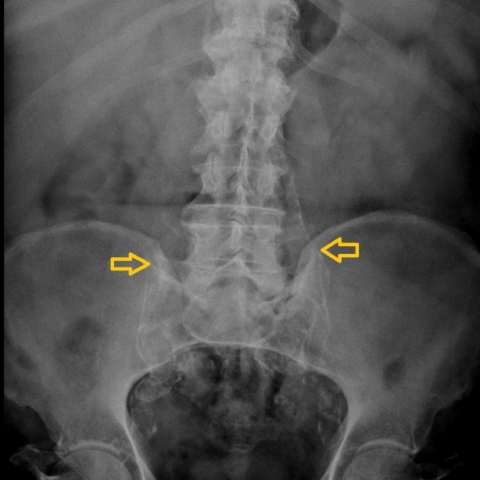

Aneurisma aórtico abdominal con fístula a la vena cava inferior